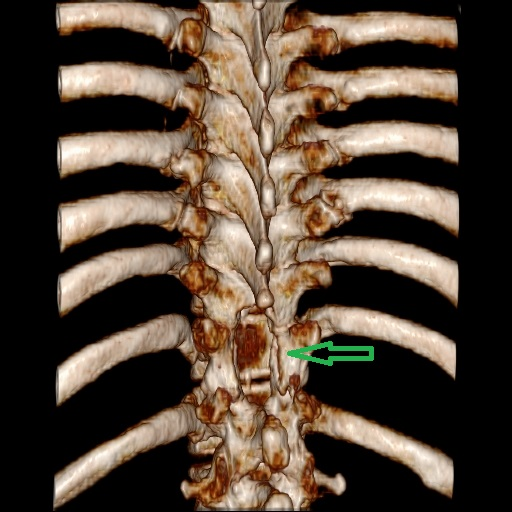

患者康婆婆(化名)今年已近70岁,因“右下肢麻木5+月加重伴疼痛3+月”前来医院治疗,行腰部核磁检查发现胸11椎体平面脊髓内囊性占位,考虑室管膜瘤的肿瘤性病变。患者下肢长期麻木伴疼痛,经神经外科医疗团队研究讨论,为患者行了微创的胸椎椎管骨质切开和脊髓内肿瘤病变的切除手术治疗,切除了患者的肿瘤后,患者下肢肌力和麻木感明显改善。

术后手术图片